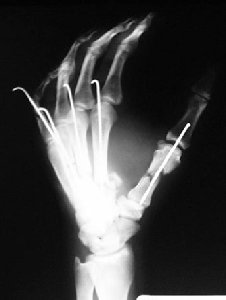

Paziente giunto all’osservazione clinica dopo alcuni giorni di trattamento eseguito in urgenza.

Alla rimozione dei fili di K. si segnala una rigidità in estensione del 2° e 3° dito da effetto tenodesi ( aderenza apparato estensore )

Risultato radiografico a distanza.